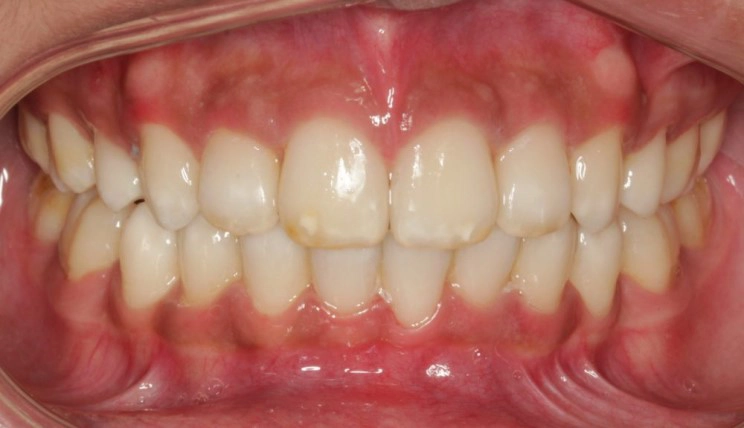

Posterior Crossbite

Posterior crossbite is the abnormal labiolingual relationship between one or more upper and lower posterior teeth, resulting in the upper teeth being positioned lingual to the lower teeth, or the upper teeth being positioned so buccal to the lower teeth their lingual face slides against the lowers buccal face.

Patient Information:

Age: 24

Gender: Female

Invisalign Treatment Option: Invisalign Comprehensive

Total Treatment Time:

29 months